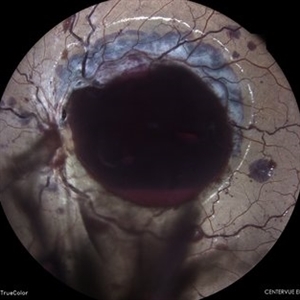

MACULAR COLOBOMA

COLOUR FUNDUS PHOTOGRAPH OF A 32 YEAR OLD MALE WITH MACULAR COLOBOMA

Photographer: Dr. Akansha Sharma-Retina Foundation, Ahmedabad

Condition/keywords: coloboma of macula